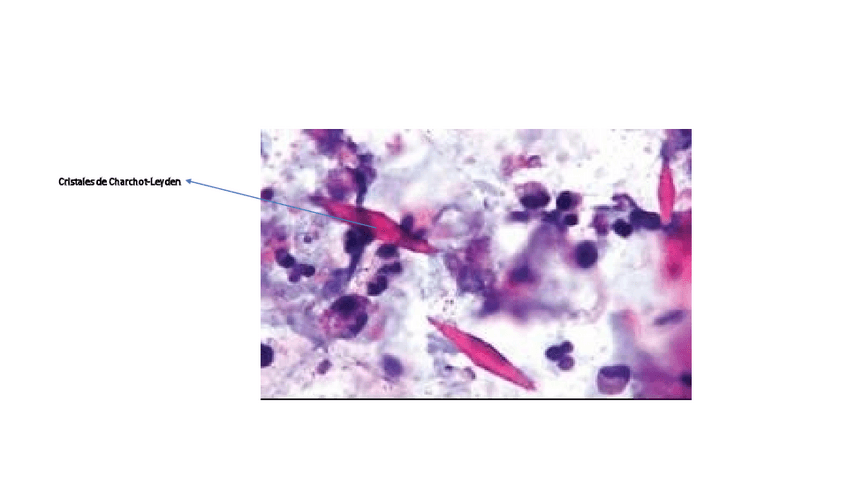

He publicado nuevos trabajos de Citología general: Liquido-Pleural.pdf

19 páginas